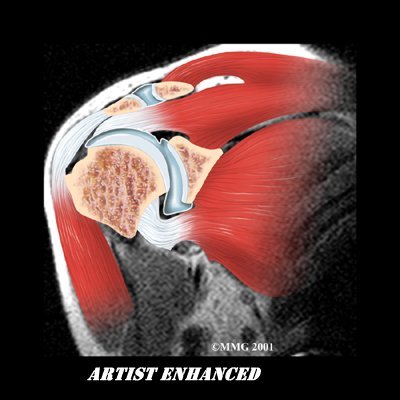

The shoulder is made up of three bones: the scapula (shoulder blade), the humerus (upper arm bone), and the clavicle (collarbone). The joint capsule is a watertight sac that encloses the joint and the fluids that bathe and lubricate it. The walls of the joint capsule are made up of ligaments. Ligaments are soft connective tissues that attach bones to bones. The joint capsule has a considerable amount of slack (loose tissue), so the shoulder is unrestricted as it moves through its large range of motion.

The shoulder is made up of three bones: the scapula (shoulder blade), the humerus (upper arm bone), and the clavicle (collarbone). The joint capsule is a watertight sac that encloses the joint and the fluids that bathe and lubricate it. The walls of the joint capsule are made up of ligaments. Ligaments are soft connective tissues that attach bones to bones. The joint capsule has a considerable amount of slack (loose tissue), so the shoulder is unrestricted as it moves through its large range of motion.

Simple X-rays are usually not helpful. An arthrogram may show that the shoulder capsule is scarred and tightened. The arthrogram involves injecting dye into the shoulder joint and taking several X-rays. In adhesive capsulitis, very little dye can be injected into the shoulder joint because the joint capsule is stuck together, making it smaller than normal. The X-rays taken after injecting the dye will show very little dye in the joint.

As your ability to move your shoulder increases, your doctor may suggest additional tests to differentiate between primary adhesive capsulitis and secondary adhesive capsulitis (from an underlying condition, such as impingement or a rotator cuff tear). Probably the most common test used is magnetic resonance imaging (MRI). An MRI scan is a special imaging test that uses magnetic waves to create pictures that show the tissues of the shoulder in slices. The MRI scan shows tendons and other soft tissues as well as the bones.

The final and most accurate diagnosis is made when an arthroscopic exam is done. The arthroscopic exam makes it possible to identify exactly which stage of disease you may be in. Tissue samples taken from inside and around the joint are examined under a microscope.

The shoulder is made up of three bones: the scapula (shoulder blade), the humerus (upper arm bone), and the clavicle (collarbone). The joint capsule is a watertight sac that encloses the joint and the fluids that bathe and lubricate it. The walls of the joint capsule are made up of ligaments. Ligaments are soft connective tissues that attach bones to bones. The joint capsule has a considerable amount of slack (loose tissue), so the shoulder is unrestricted as it moves through its large range of motion.

The shoulder is made up of three bones: the scapula (shoulder blade), the humerus (upper arm bone), and the clavicle (collarbone). The joint capsule is a watertight sac that encloses the joint and the fluids that bathe and lubricate it. The walls of the joint capsule are made up of ligaments. Ligaments are soft connective tissues that attach bones to bones. The joint capsule has a considerable amount of slack (loose tissue), so the shoulder is unrestricted as it moves through its large range of motion. As the name suggests, adhesive capsulitis affects the fibrous ligaments that surround the shoulder forming the capsule. The condition referred to as a frozen shoulder usually doesn't involve the capsule. Secondary adhesive capsulitis (or true frozen shoulder) might have some joint capsule changes but the shoulder stiffness is really coming from something other than the joint capsule. Some of the conditions associated with secondary adhesive capsulitis include rotator cuff tears, biceps tendinitis, and arthritis. In either condition, the normally loose parts of the joint capsule stick together. This seriously limits the shoulder's ability to move, and causes the shoulder to relatively freeze.